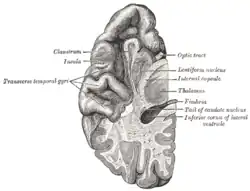

O lobo temporal é um dos quatro lobos principais do córtex cerebral no cérebro dos mamíferos . O lobo temporal está localizado abaixo da fissura lateral em ambos os hemisférios cerebrais do cérebro dos mamíferos.[1]

Estrutura

O lobo temporal consiste em estruturas vitais para a memória declarativa ou de longo prazo. A memória declarativa (denotativa) ou explícita é a memória consciente dividida em memória semântica (fatos) e memória episódica (eventos).[3] As estruturas do lobo temporal medial que são críticas para a memória de longo prazo incluem o hipocampo, juntamente com a região hipocampal circundante que consiste nas regiões neocorticais perirrinal, parahipocampal e entorrinal.[3] O hipocampo é crítico para a formação da memória, e o córtex temporal medial circundante é atualmente teorizado como crítico para o armazenamento da memória.[3] Os córtices pré-frontal e visual também estão envolvidos na memória explícita.[3]